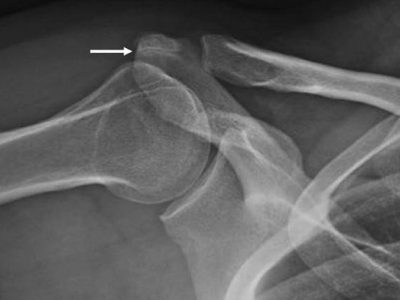

Osacromiale is a condition where the acromion, the prominent bone at the top of your shoulder, fails to fuse fully during development. This bone typically develops from three ossification centers—meta-acromion (base), meso-acromion (middle), and pre-acromion (tip)—which should generally fuse by…